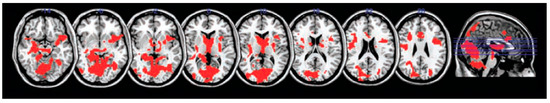

- Sekeres, M.J.; Winocur, G.; Moscovitch, M.; Anderson, J.A.E.; Pishdadian, S.; Martin Wojtowicz, J.; St-Laurent, M.; McAndrews, M.P.; Grady, C.L. Changes in Patterns of Neural Activity Underlie a Time-Dependent Transformation of Memory in Rats and Humans. Hippocampus 2018, 28, 745–764. [Google Scholar] [CrossRef] [PubMed]

- Sekeres, M.J.; Moscovitch, M.; Winocur, G.; Pishdadian, S.; Nichol, D.; Grady, C.L. Reminders Activate the Prefrontal-medial Temporal Cortex and Attenuate Forgetting of Event Memory. Hippocampus 2021, 31, 28–45. [Google Scholar] [CrossRef] [PubMed]